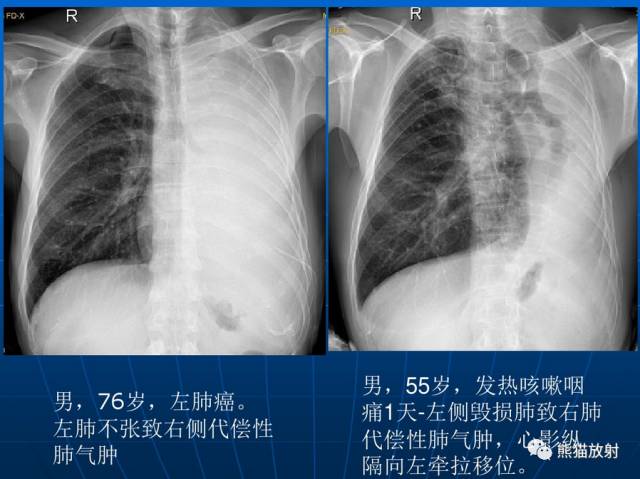

代偿性肺气肿属于局限性非阻塞性肺气肿,是由于一部分肺的纤维化或不张,或手术切除后,余肺膨胀代偿其胸腔内失去的体积所致。

代偿性肺气肿的范围和程度取决于肺部切除的多少或肺萎缩的情况。如果一侧肺完全切除或不张,对侧的肺可全部产生代偿性肺气肿,甚至形成纵隔疝。一叶、一段或少于一叶的代偿性肺气肿较为常见。由于其范围小,一般不产生明显的胸廓、横膈或心脏和纵隔的改变。